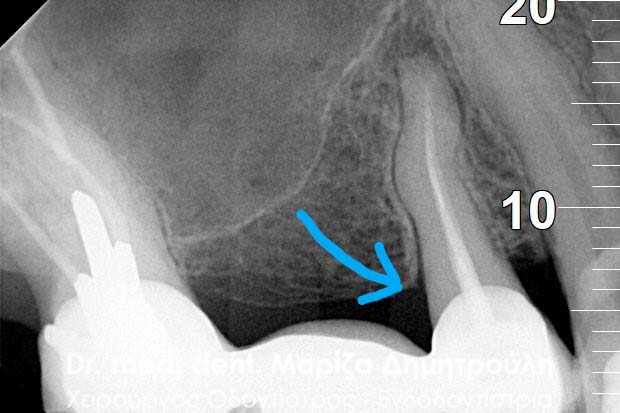

BEFORE

AFTER